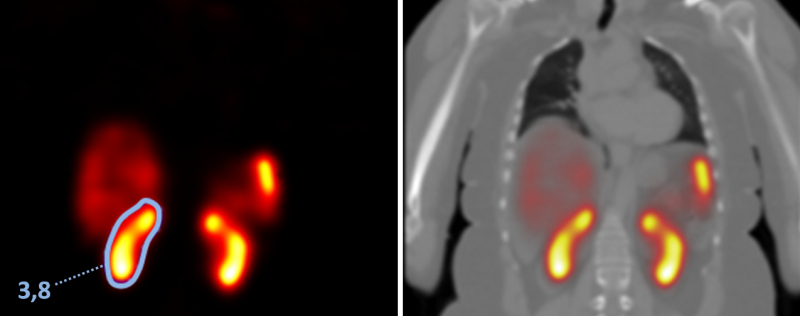

A conversão das imagens paramétricas de dose (Gy) para formato DICOM permitiram a sua abertura no programa de processamento de imagem OsiriX e OsiriX MD, com a possibilidade de fusão à CT e definição de VOIs em órgãos de captação fisiológica e em tumores (Fig. 3).

Os intervalos das aquisições e as doses nas estruturas analisadas nos estudos PET com 68Ga-DOTATATE e SPECT com 177Lu-DOTATATE são apresentados nas Tabelas 1 e 2.